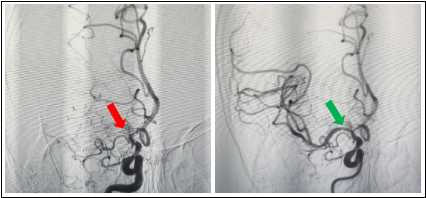

右侧大脑中动脉慢性闭塞再通前后对比图

右侧大脑中动脉球囊扩张治疗前后对比图